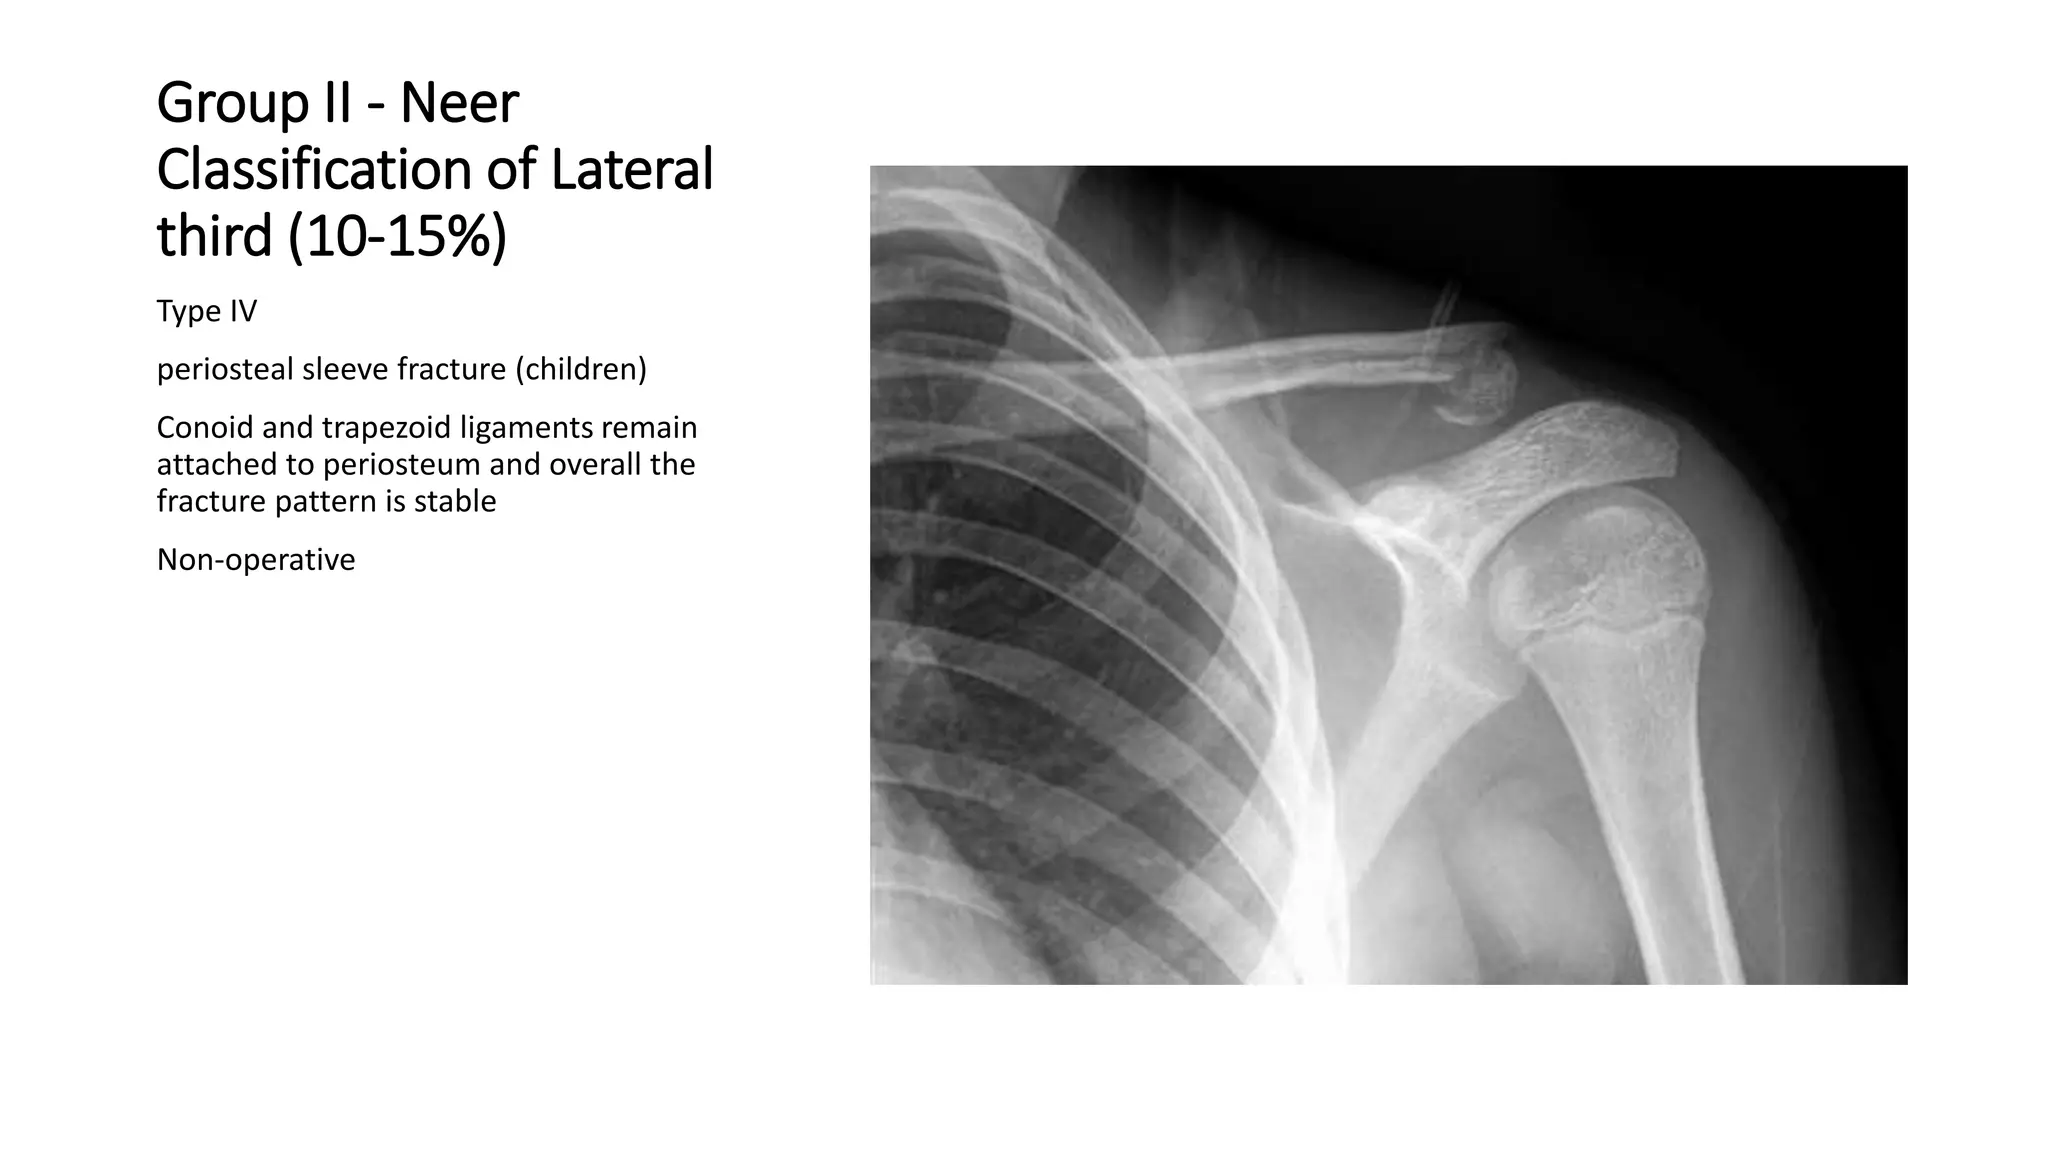

Group II - Neer

Classification of Lateral

third (10-15%)

Type IV

periosteal sleeve fracture (children)

Conoid and trapezoid ligaments remain

attached to periosteum and overall the

fracture pattern is stable

Non-operative